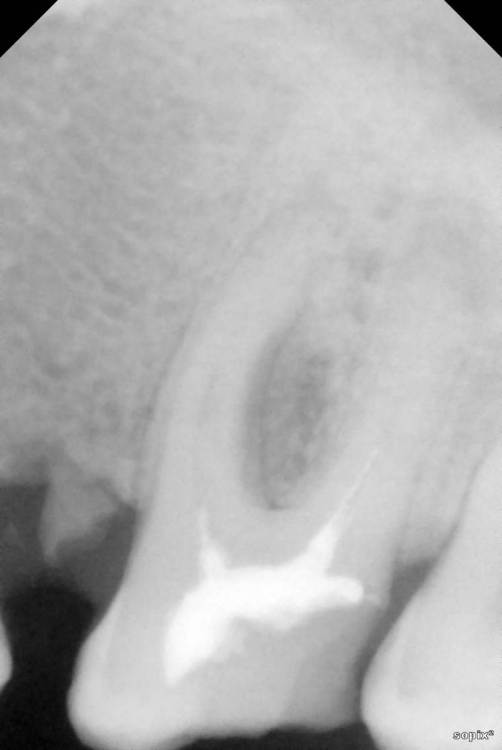

Siegfrid Опубликовано 29 июля, 2021 Поделиться Опубликовано 29 июля, 2021 Был у нескольких врачей в разных клиниках и мнения разошлись. В двух клиниках нашли проблемы сумма оказалась большой сходил в недорогую клинику, там проблемы не видят.. 2.6 и 2.7 Зуб со свищем 2 разных врача берутся лечить с шансом примерно 40% на успех, 1 врач говорит что только удаление. Ссылка на комментарий

Siegfrid Опубликовано 30 июля, 2021 Автор Поделиться Опубликовано 30 июля, 2021 Между зубами 2.6 и 2.7 набивается еда и гниет, когда я пошел в клинику на консультацию когда сделали снимок нашли что также плохо полечены каналы и для полного лечения двух зубов оказалась большая сумма которой у меня нету, я об этом сказал тогда мне предложили перепломбировать чтобы не набивалась еда, предупредив что непролеченные каналы со временем приведут к потере зубов. Я сходил в другую клинику, врач нашел кариес на одном из этих зубов но так как уходил в отпуск записал к другому врачу этого же заведения, я дожался своей очереди и вот он не видит проблем с зубами кроме того что со свищем. Что мне делать дальше? Ссылка на комментарий

St. Опубликовано 30 июля, 2021 Поделиться Опубликовано 30 июля, 2021 Добрый день. В верхних зубах есть большие пломбы с кариесом между зубами. Нужно покрыть их коронками, предварительно перелечив каналы. Если финансово пока не готовы к этому, то возможно временно откорректировать пломбы или сделать временные пластмассовые коронки. С нижним зубом рекомендации такие же - перелечить каналы и покрыть коронкой 1 Ссылка на комментарий